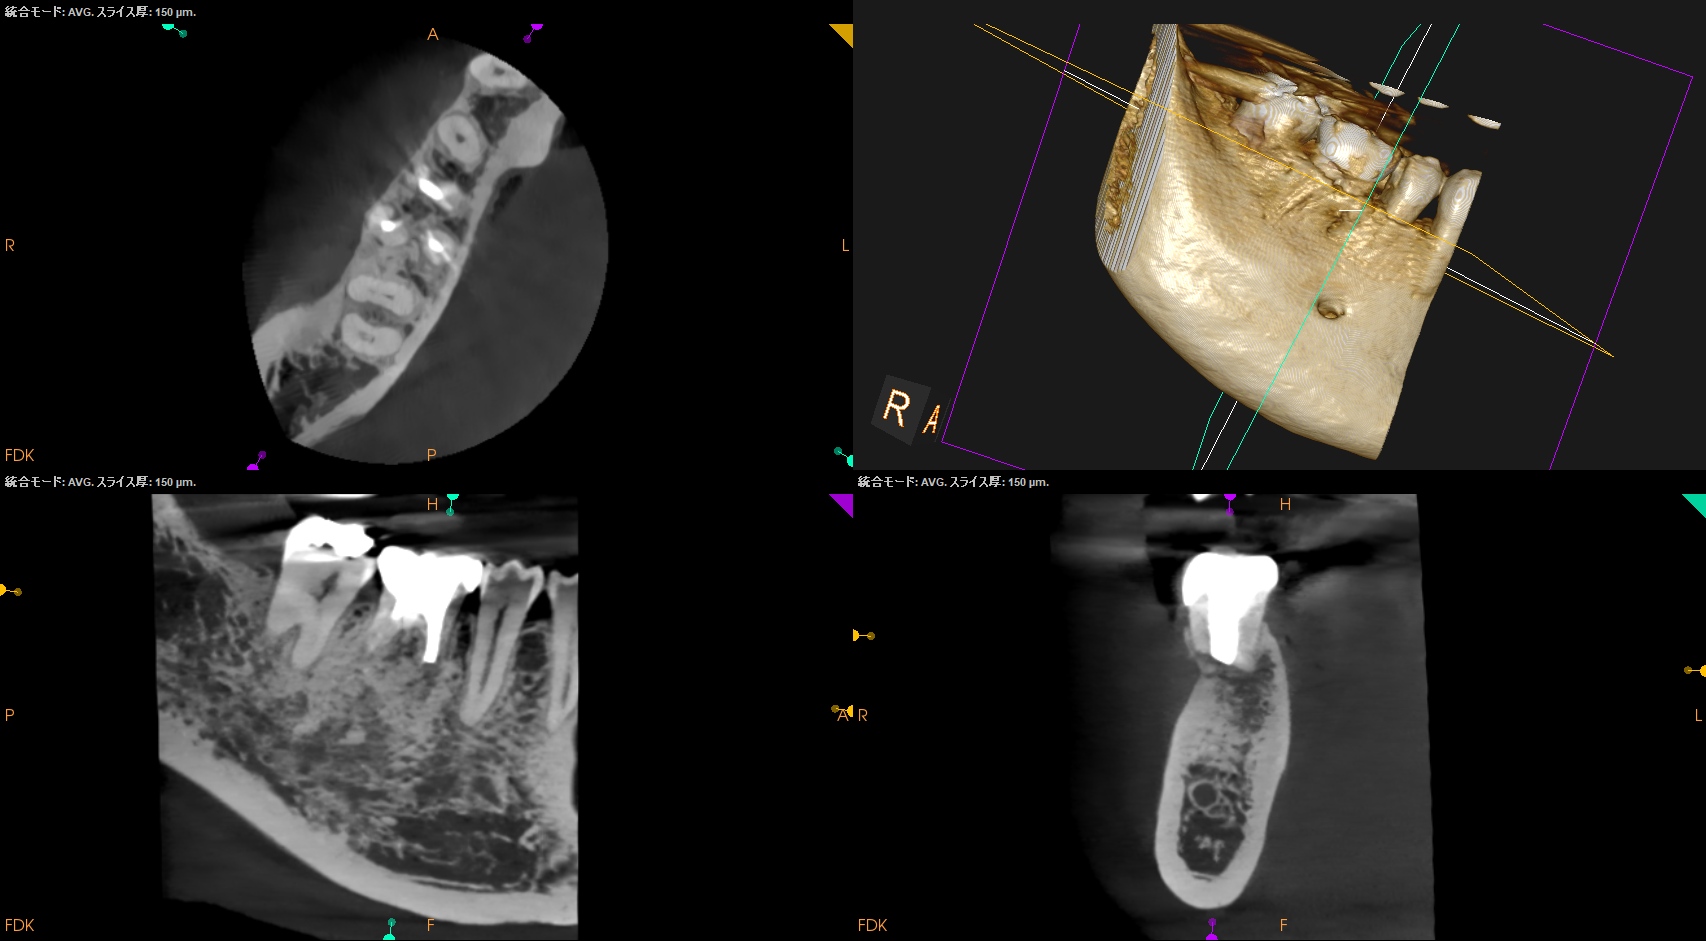

#30 M Apicoectomy, D+Radix Re-RCT 2yr recall(2025.10.17)

Radix

初診時、1年後と比較した。

トランスポーテーションしたMは劇的に治癒している。

Dも然りだ。

が、トランスポーテーションしているRadixはまだ治癒途中だろう。

が、患者さんに症状もないことからこの歯の状況はさらに2年後に経過を見せてもらうこととなった。

次回が、#30 M Apicoectomy, D+Radix Re-RCT 4yr recallとなる。